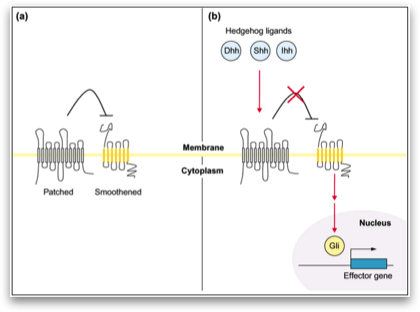

To elucidate the molecular mechanisms of pancreatic cancer, our group has steadily been working on the signal-transduction in this tumor. The objective of this project was the activation of the hedgehog signal transduction pathway, triggered by hedgehog binding to the transmembrane receptor patched 1 (PTCH1) or by mutations in the PTCH1 gene. Activation of the hedgehog signal transduction pathway, triggered by hedgehog binding to the transmembrane receptor patched 1 (PTCH1) or by mutations in the PTCH1 gene, plays an important role in the development of various tumors.

In the present study, we show that the Hedgehog target genes PTCH1 and GLI1 are up- regulated in pancreatic adenocarcinoma in comparison to re- spective normal pancreatic tissue, indicating that the Hedgehog signaling pathway is activated in this tumor entity. Hedgehog activation seems to be mediated mainly through aberrant ligand overexpression like up-regulation of SHH or IHH in pancreatic cancer cells. Interestingly, a direct comparison of SHH and IHH expression in our tumor samples with the corresponding normal pancreatic tissue did not reveal any significant differences (data not shown), indicating that alternative mechanisms might contribute to increased Hedgehog pathway activity in pancreatic cancer cells. To analyze if the Hedgehog pathway activation func- tions via alterations in the PTCH1 gene, like it is known in me- dulloblastoma21 and patients with the nevoid basal cell carcinoma syndrome,11,22 we performed the first screen for PTCH1 gene mutations in 36 pancreatic adenocarcinoma biopsies. Using SSCP- analysis and direct sequencing, we identified polymorphisms in exons 11, 12, and 22 of the PTCH1 gene, but no somatic PTCH1 mutations indicating that genetic PTCH1 alterations are not responsible for the Hedgehog activation in pancreatic adenocarcinoma.

On the basis of the results of our mRNA expression analy- sis indicating Hedgehog pathway activation in pancreatic cancer, we inhibited the Hedgehog pathway with cyclopamine. To investigate whether the growth-inhibitory effect of cyclo- pamine may be related to inhibition of the Hedgehog signaling pathway, we used a GLI1 luciferase reporter assay. Transfection of the cells with a GLI1 luciferase reporter or with a nonfunctional GLI1 promoter variant indicated significant basal hedgehog ac- tivity in Capan-1 (Fig. 6A). Next, the pancreatic adenocarcinoma cells were treated with increasing amounts of cyclopamine. As shown in Figure 6B, in particular, Capan-1 showed a strong reduced viability for 3 days compared with the cells treated with PBS.